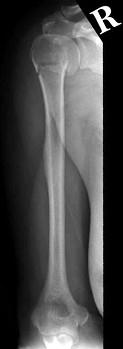

问题 图示骨折的分类有( )

选项 A、内收型骨折 B、无移位骨折 C、粉碎型骨折 D、外展型骨折 E、压缩骨折

答案 BCE